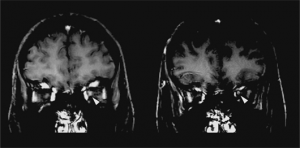

Neuroimaging is helpful in diagnosing ADEM. At presentation, MRI findings may be similar between MS and ADEM. In patients with ADEM, T2-weighted and fluid attenuated inversion recovery (FLAIR) brain MRI typically shows large, bilateral, hyperintense, lesions (>1-2 cm) that are diffuse and poorly demarcated.[22] ADEM lesions can involve both the white and gray matter, affecting the subcortical and central white matter, cortical gray-white matter junction, and deep gray matter of the basal ganglia, thalami, cerebellum, brainstem, with very rare T1 hypointense “black hole” white matter lesions that are more typically seen in MS.[14][22] Gadolinium enhancement of ADEM lesions is found in only 30% of cases.[35]

Key brain MRI features found in ADEM that are absent in MS include periventricular sparing without Dawson fingers (ovoid lesions perpendicular to lateral ventricles), both deep gray matter and cortical involvement, bilateral and diffuse lesions that are large, globular, and poorly demarcated.[22] In 1/3 of cases, spinal cord demyelination is seen over multiple segments. Diffusion-weighted imaging (DWI) can help elucidate the timing of the demyelinating event.[39] In the first week following ADEM onset, DWI will show decreased diffusivity. This is thought to be a result of inflammation causing myelin sheath edema and accumulation of inflammatory cells, impeding the migration of water molecules. After the first week, the extracellular space widens, causing increased water diffusivity on DWI.[39]